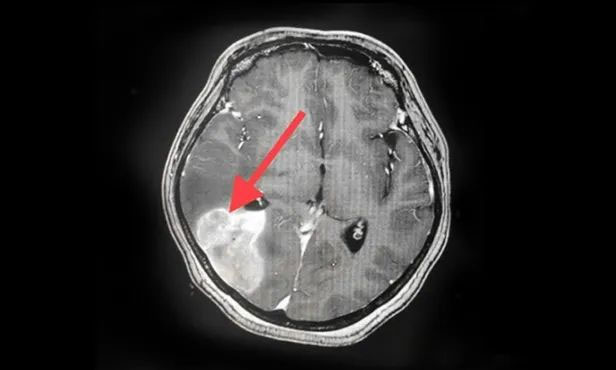

▲ 剛?cè)朐簳r(shí)病灶影像

▲ 完成穿刺,黑色囊液被順利引流

▲ 經(jīng)復(fù)查,病灶較前明顯縮小

按照腫瘤復(fù)查的標(biāo)準(zhǔn),復(fù)查影像顯示王女士顱內(nèi)病灶相較于來院時(shí)明顯縮小。家屬為此特意向陳琦主任致謝,并對(duì)醫(yī)院的治療和服務(wù)表達(dá)了充分肯定。